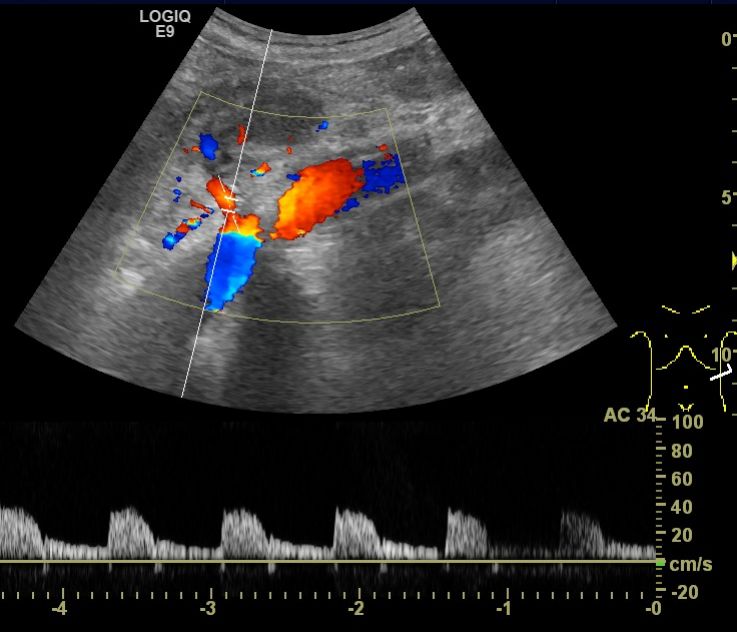

(2)肾血管病变引起的高血压患者中,以肾动脉硬化为著,彩色多普勒超声多表现为肾动脉血流速度增快、加速时间延长、血流阻力指数升高,二维超声还可以测量动脉管腔及内径等准确的判断肾动脉情况,为临床治疗提供可靠的依据。

图2